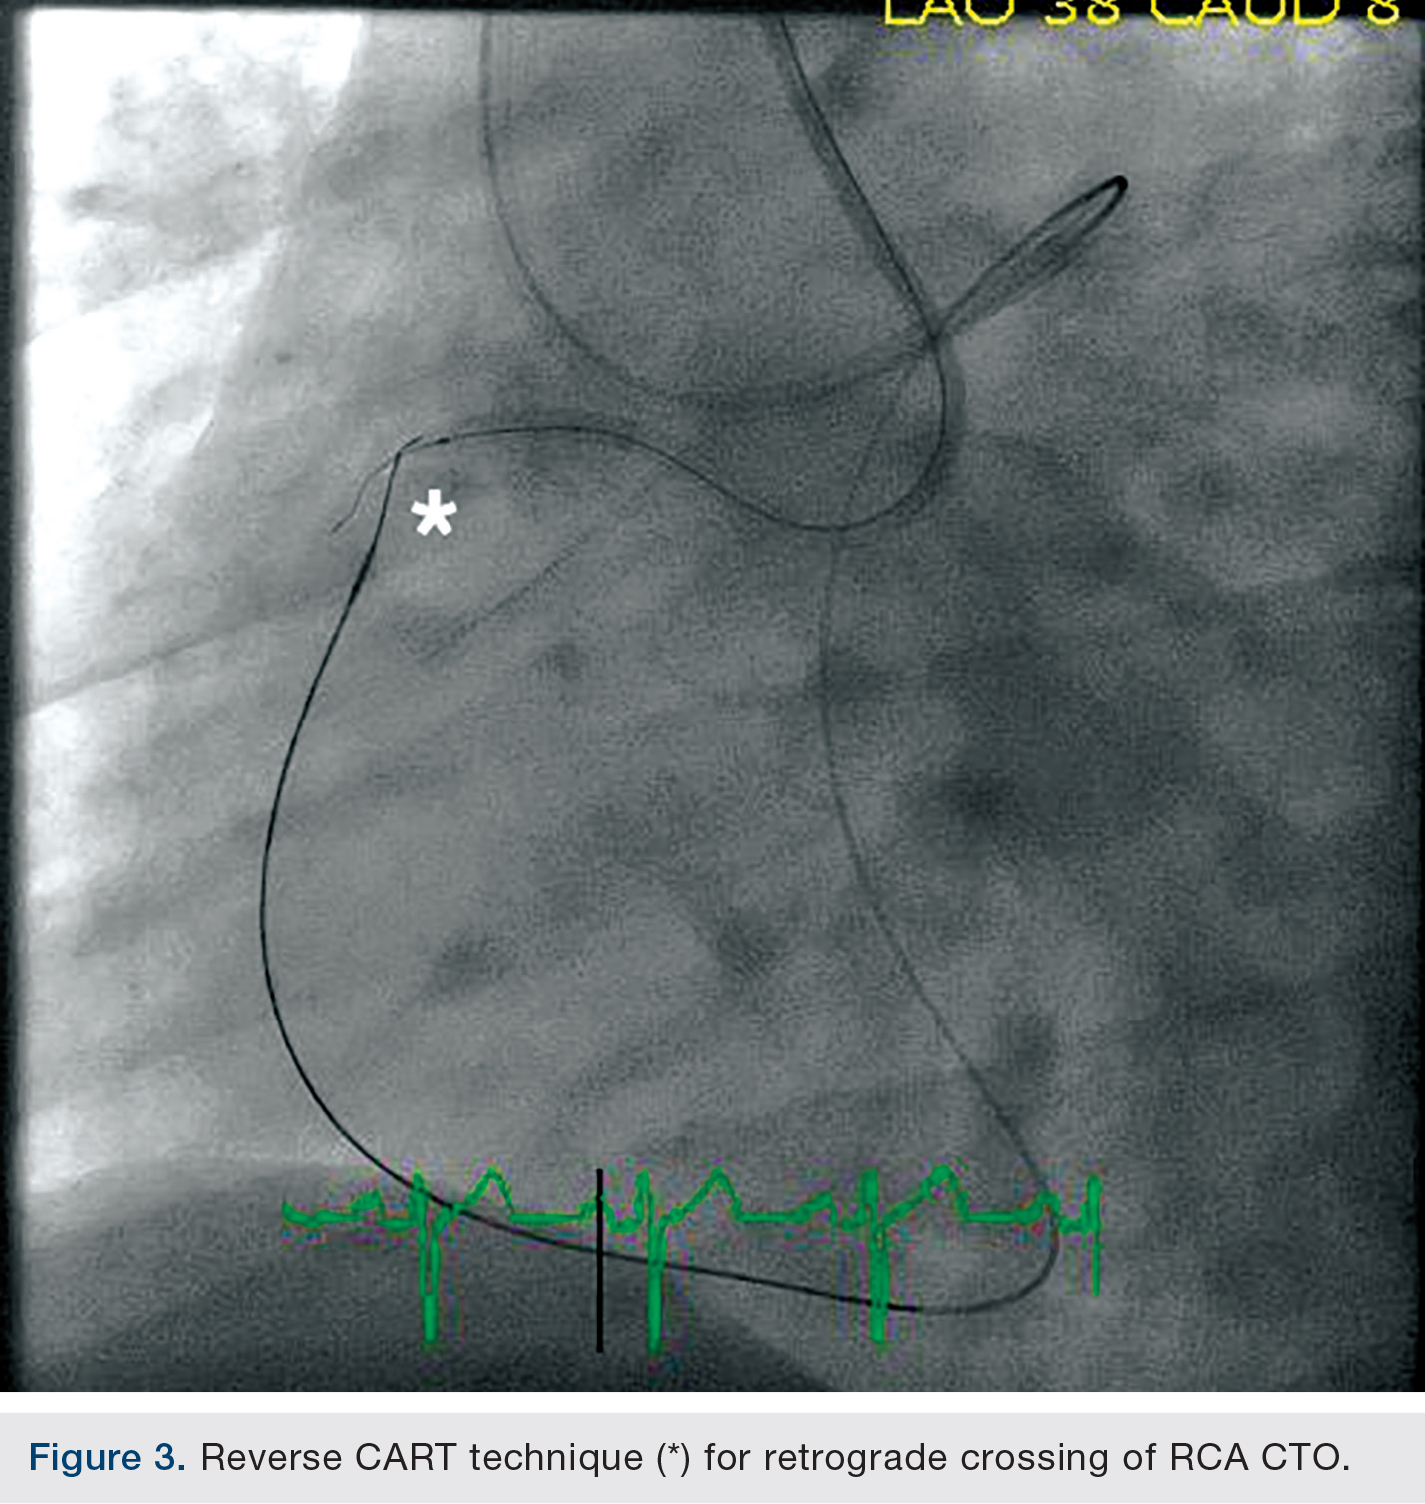

Once the wire was advanced all the way to the proximal CTO in the RCA, the proximal cap proved to be difficult to cross and a reverse controlled antegrade and retrograde subintimal tracking (CART) technique was utilized (Figure 3). This entailed creating a dissection plane channel proximally in the RCA using a small 1.25mm over-the-wire balloon and a Confianza Pro 12 wire (Abbott Vascular) that was advanced proximally from the RCA AL-1 guide in an antegrade maneuver. The septal Fielder XT wire was then exchanged over the Corsair for an Asahi Miracle Bros 4.5 wire (Abbott Vascular), advanced through the calcific proximal cap and into the RCA AL-1 guide, and externalized via the RCA guide.The RCA lesion was then pre-dilated and stented with a total of four drug-eluting stents in overlapping fashion, up to but short of the ostium.